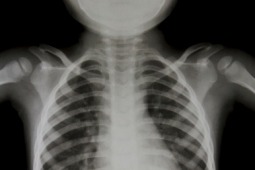

Badacze amerykańscy dokonali analizy parametrów klinicznych (w tym laboratoryjnych), które pozwoliłyby na wyodrębnienie populacji chorych szczególnie narażonych na zajęcie tkanki płucnej w przebiegu IMZ i wskazywałyby na konieczność wykonania badań czynnościowych płuc. Częstość wtórnych zmian płucnych w przebiegu IMZ u dzieci, szacuje się na 18-50%. Dotychczas w większości dane o możliwym związku badań czynnościowych płuc i parametrów klinicznych (np. obecność swoistych dla zapalenia mięśni autoprzeciwciał) pochodzą z badań nad populacją osób dorosłych. Analiza przypadków 38 dzieci w wieku 6-23 lata z pewnym/prawdopodobnym rozpoznaniem IZM wykazała związek takich parametrów klinicznych jak: obecność przeciwciał swoistych dla zapaleń mięśni oraz innych autoprzeciwciał związanych z chorobą układową, zwiększone stężenie neopteryny i aldolazy w surowicy, starszy wiek w chwili rozpoznania, a także krótki okres czasu do ustalenia rozpoznania, wskaźnik CMAS (Childhood Myositis Assessment Scale) - z nieprawidłowymi badaniami czynnościowymi płuc. Nieprawidłowości w badaniach czynnościowych , które poddano ocenie to pojemność dyfuzyjna dla tlenku węgla (DLCO) oraz TLC (całkowita pojemność płuc). Wartości nieprawidłowe TLC lub DLCO (poniżej 80% wartości należnej) stwierdzono u 37% badanych.